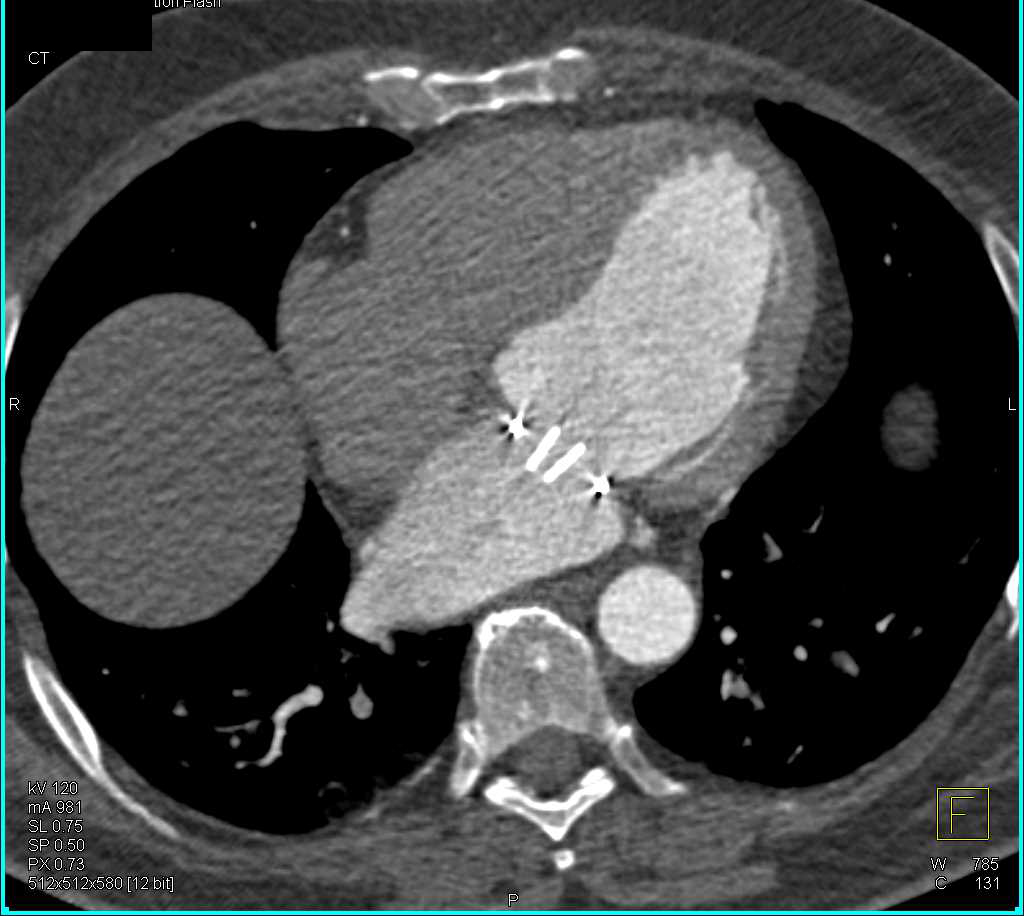

GSW Near Left Posterior Knee Fossa with Occlusion of Distal Superficial Femoral Artery (SFA) and Popliteal Artery